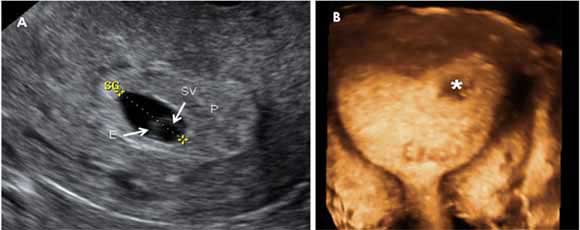

Ecografía de 5 semanas con sonda vaginal

Este examen ecográfico de un embarazo de 5,6 semanas está realizado con sonda vaginal. A la derecha (A), se aprecia el saco gestacional (SG), la zona de las vellosidades coriales (P) que dará lugar a la futura placenta, el saco vitelino (SV) y el embrión (E), que mide 5 milímetros y ya tiene latido cardiaco visible por ecografía. A la izquierda (B), se observa una vista panorámica del útero con el embarazo (*), alojado en la zona del cuerno derecho uterino.

El latido cardiaco puede apreciarse hacia la quinta semana y cuatro días. Un embrión de 5 milímetros (correspondiente al inicio de la sexta semana) o más debe tener siempre latido cardiaco.